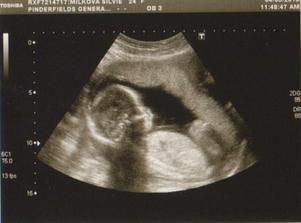

dnes jsme dostali výsledek z NT screaningu! Je to 1:100000 🙂)))